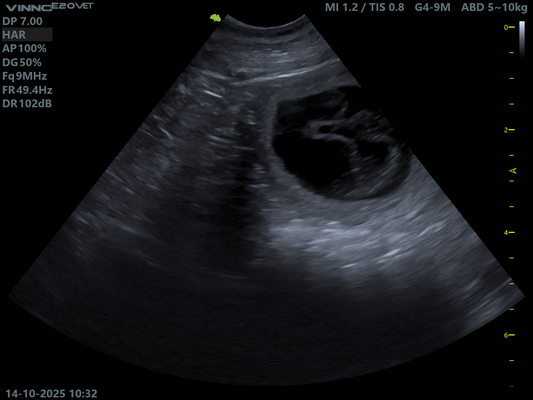

14.10.2025 Ultraschall Untersuchung.

Schon nach einem kurzen Blick in Ruby's Bauch war klar.

Sie ist tragend!

Doch wie viele es werden bleibt bis zuletzt spannend.

Hier müssen wir uns absolut keine Sorgen machen. Ruby scheint einen normalen Wurf zu erwarten, so auch die Aussage unserer Tierärztin.